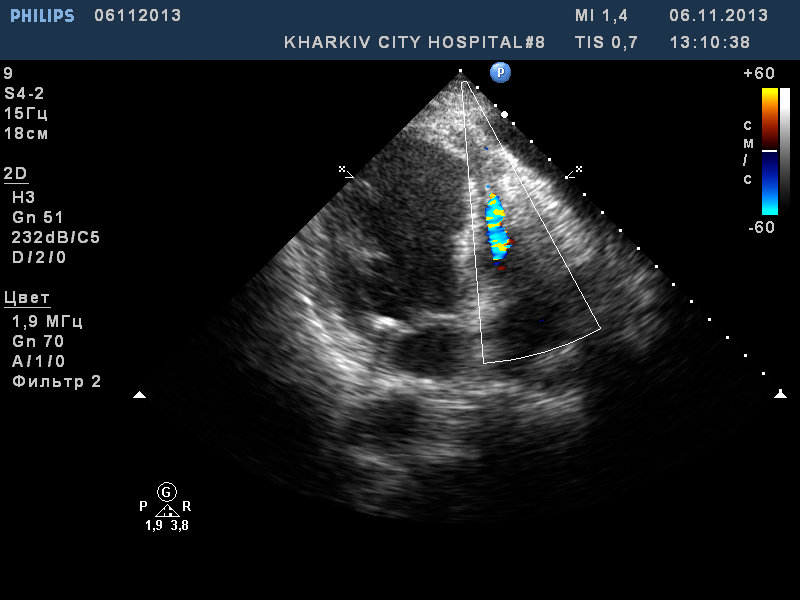

Пациентка 58 лет с оит. Смотрел накануне- картина инфаркта - акинезия передне-перегородочного, верхушечного сегментов ЛЖ. Находилась в оит. Доктора через несколько дней обнаружили что добавился шум отсутствующий ранее. Возникло подозрение на отрыв хорд МК.

При ЭХО-КС картина перфорации верхушечного сегмента МЖП.

из этой серии . Пациентка с инфарктом. Картина разрыва МЖП.